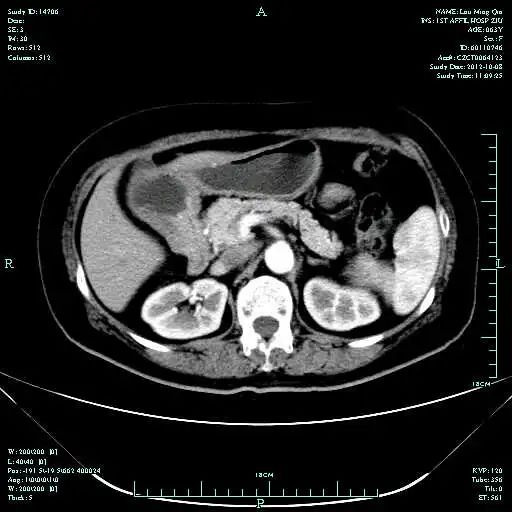

CT-T

CT-H1

影像学检查结果评估:cPD。

疗效评估:cPR